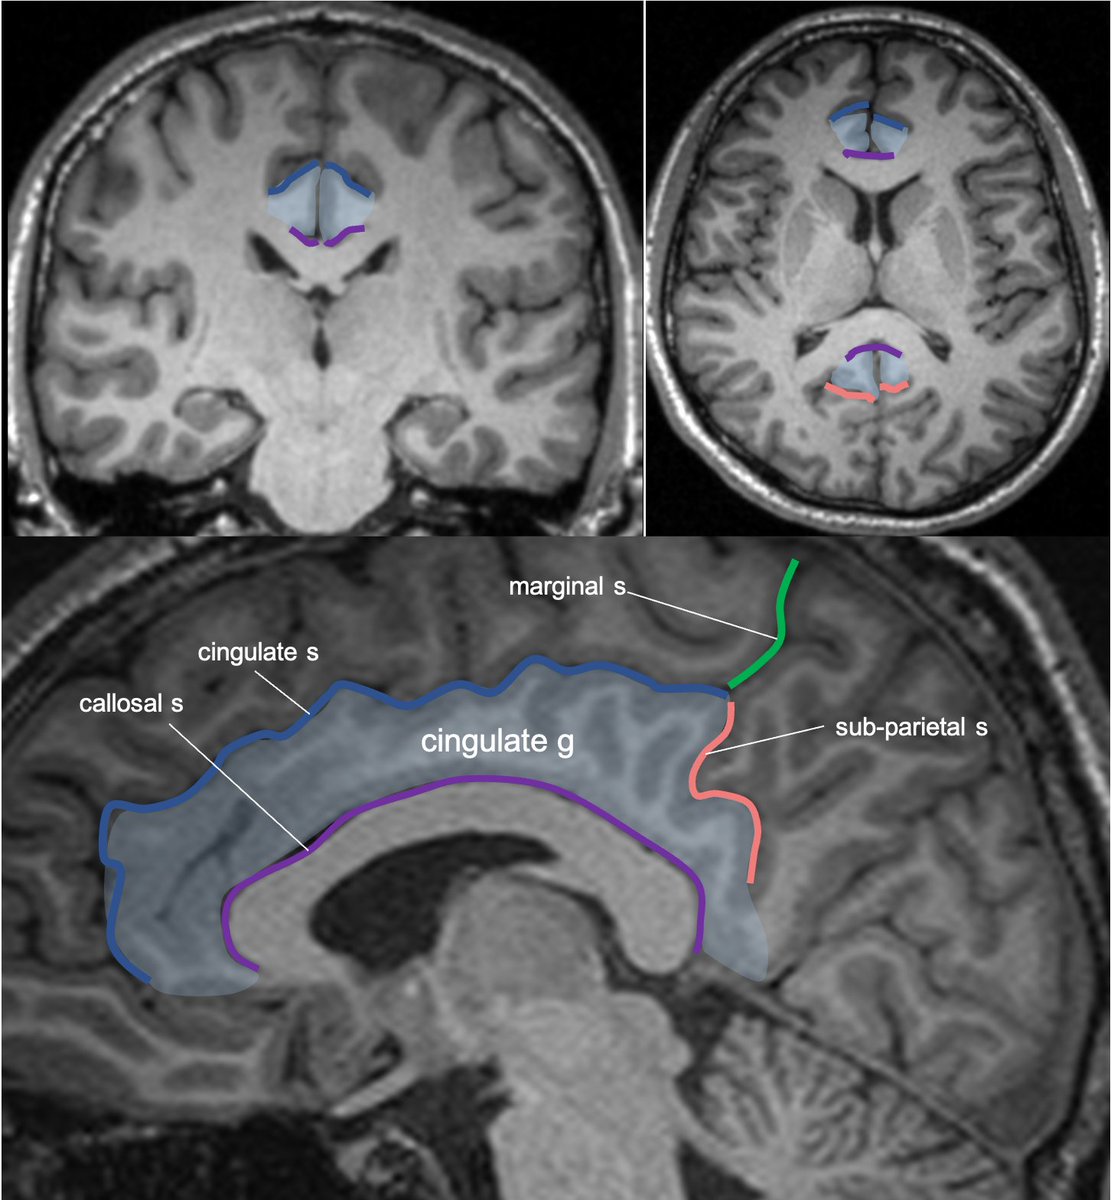

Gyral anatomy of the medial brain surface: calcarine sulcus divides the cuneus from lingual gyrus at the med occ lobe. The lingual g continues anteriorly along the med/ inferior temporal lobe. The cingulate g wraps sup & posterior to corpus callosum along the medial brain.

Cingulate g. is part of the limbic circuit; the post cingulate cortex (PCC) is important in default mode network, awareness, pain, and episodic memory retrieval. PCC including the retrosplenial cortex (which together some call restrosplenial gyrus) is involved by the tumor. 11/13